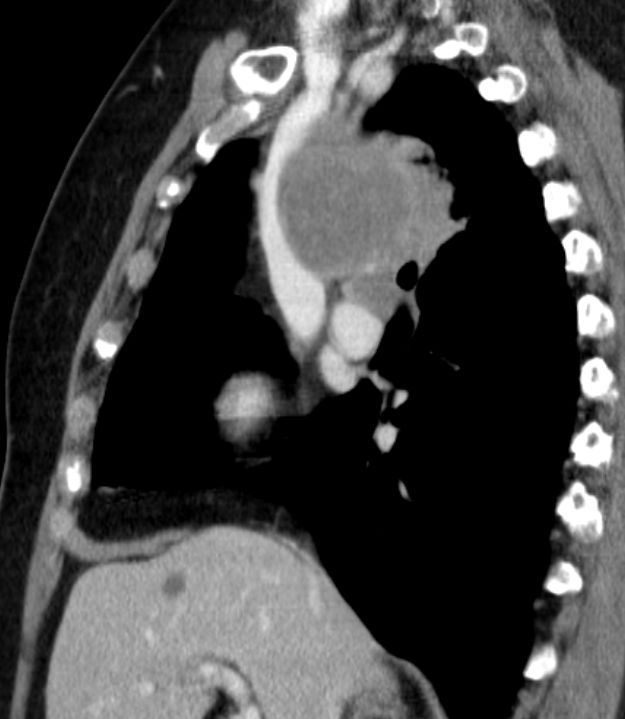

65-jähriger Mann mit einem SCLC rechts zentral, G3,Ki67 90%, chromogranin – negativ, CD56 negativ, CD45 negativ, Pankeratin z.T. positiv.![]() |

![]() |